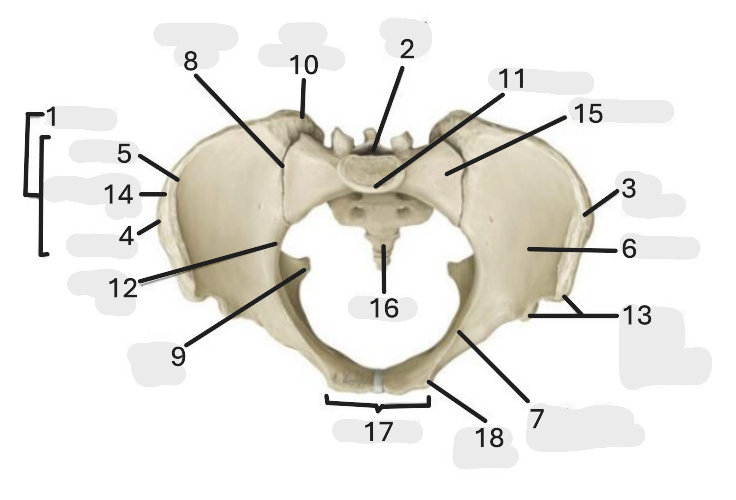

Where is the pelvic inlet

1

Where is the sacro-iliac joint

2

Where is the pubic tubercle

3

Where are the S1 body

4

Where is the ischial spine

5

Where is the ala of sacrum

6

Where is the anterior superior iliac spine

7

Where is the ischiopubic ramus

8

Where is the coccyx

9

Where is the obturator foramen

10

Where is the pubic symphysis

11

Where is the ischial tuberosity

12